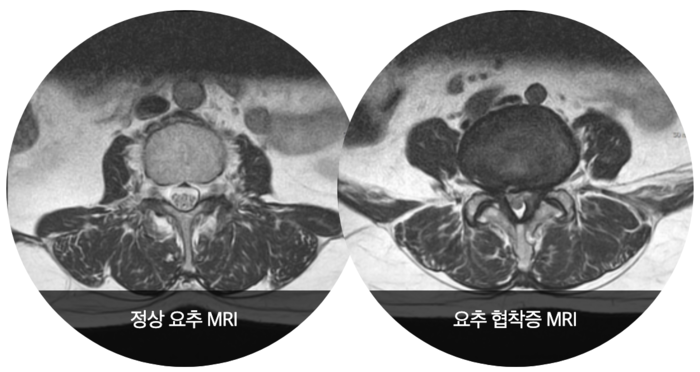

탈장은 내장을 지탱하고 있는 근육이 약해져 장이 밖으로 탈출하는 질환입니다. 보통 허벅지 부근 사타구니에서 흔히 발생하는데 이를 서경부 탈장이라고 합니다. 서경부 탈장이 다양한 탈장의 종류 중에서도 흔히 볼 수 있습니다.

탈장이 나타나면 하복부에 무거운 느낌과 통증이 나타나게 됩니다. 그런데 시간이 지나면서 통증 정도가 약해지고 무리하게 활동할 때만 통증이 발생하기 때문에 탈장인지 잘 모르시는 분들이 많습니다.

탈장은 방치함으로써 증상이 호전되는 것이 아니라 더 심해질 뿐입니다. 장이 구멍에 끼면 나올 수도 없는 상황(감쇠 현상)이 되어 위험할 수 있습니다.

이 상태가 길어지면 혈액순환이 제대로 안 돼서 장이 괴사하거나 장폐색이 발생하기도 합니다. 탈장은 진단을 받은 후 빨리 수술적 치료를 받아야 좋아집니다. 탈장수술은 선택이 아닌 필수이며 바로 치료를 해야 수술 후 재발이나 합병증을 막을 수 있습니다.